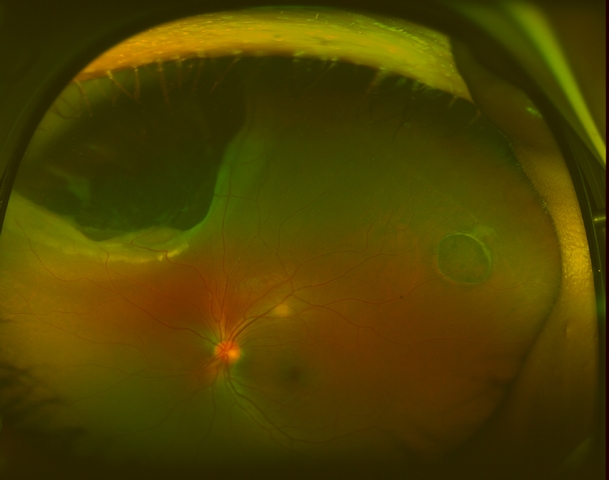

On exam, her visual acuity was 20/20 OD and 20/25 OS uncorrected. Intraocular pressures measured 16mmHg OU. Her external and anterior segment exam were unremarkable, with no evidence of inflammation. The posterior segment exam in the right eye was also unremarkable, with normal-appearing vitreous, optic nerve, macula, retinal vessels, and periphery. Examination of the left eye showed normal vitreous with no cells, normal optic nerve, and macula. In the supratemporal mid-periphery was a flat ~3 disc area CHRPE. In the supranasal periphery there was an irregular, elevated choroidal mass which involved 2 clock hours, which did not appear to extend anterior to the pars plana. The posterior aspect is anterior to the equator. The lesion was pigmented and there was trace hemorrhage overlying it. There was shallow subretinal fluid over the lesion and mild lipid exudation on its border.

Optos fundus photographs and fluorescein angiogram were performed. The angiogram showed early blockage with some mottled hyperfluorescence that increases in the later phase, with diffuse late leakage overlying the tumor.